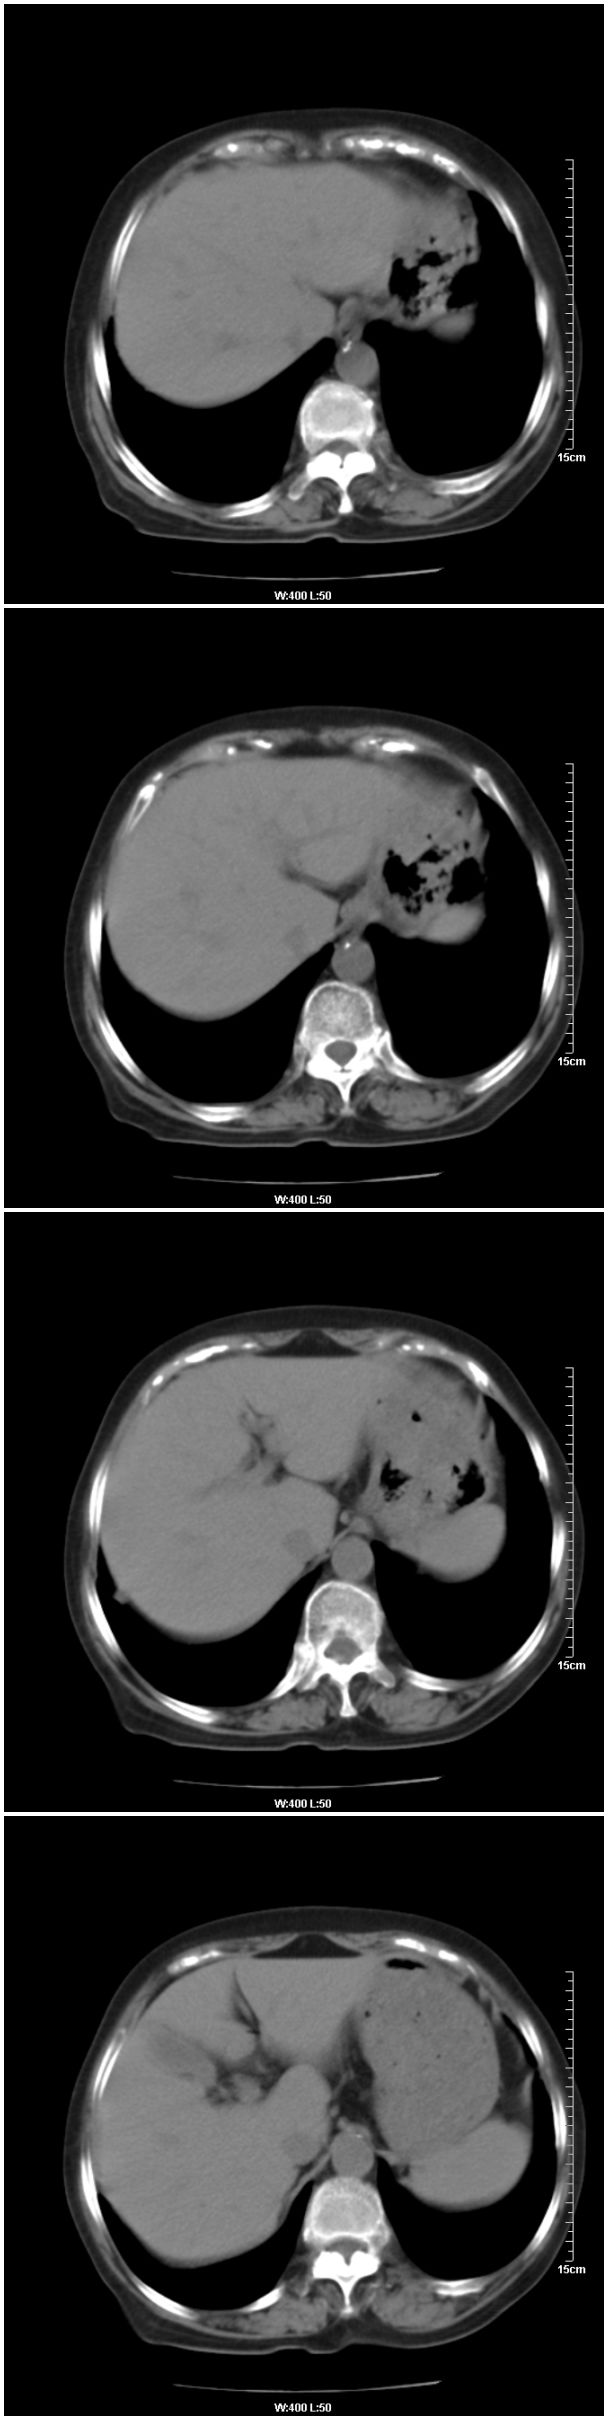

女性,78岁。术前体检发现肺部病变,看看还有什么问题?肺病变是什么性质?

本例临床是以乳腺癌的术前检查平片发现肺部病变的,请战友们看乳腺病变是否能够看出来,在哪一侧?

在右侧,支持!右肺中心型肺癌! 右乳腺肿物。

支持!右肺中叶中心型肺癌!右侧乳腺内上象限结节,建议薄扫

乳腺病变在右侧,右肺门区新生物伴右中叶阻塞性肺炎、部分部张

右肺中叶不规则肿块,管腔阻塞,心包内少量积液,支持右肺中心型肺癌。

应该是右肺中心型肺癌,乳腺的肿物应该在右侧,看见右侧有结节,并乳头凹陷

右侧乳腺内上象限结节影,边缘模糊,右肺病变相邻支气管内见软组织密度影及斑点样钙化灶,考虑肺癌可能性大,建议结合纤支镜检查。

右肺中央型肺癌伴中叶肺不张。

右乳腺内结节病灶,如增强扫描动脉期结节呈明显强化可考虑乳癌。